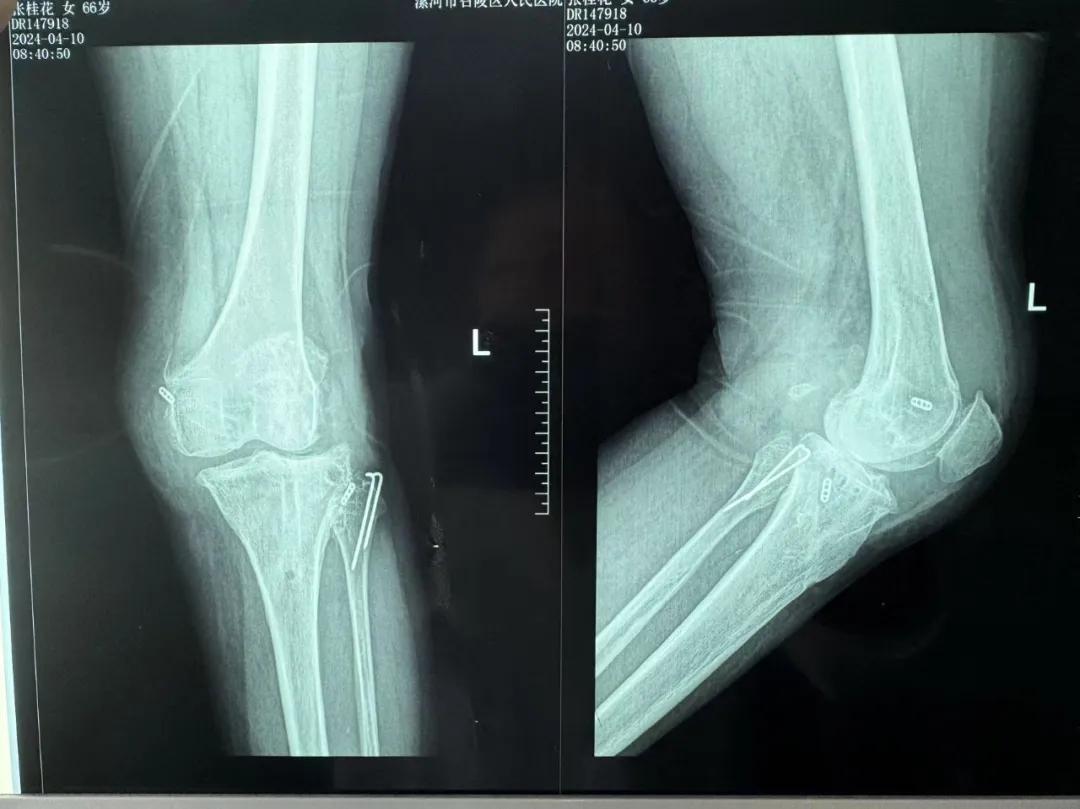

患者來院后,漯河市骨科醫(yī)院(漯河醫(yī)專二附院、漯河市立醫(yī)院)主治醫(yī)師康樂便成了她的管床醫(yī)生。在經(jīng)過詳細(xì)的術(shù)前診斷與檢查后,關(guān)節(jié)外科主任李付彬組織科室團隊針對患者的診斷情況進行術(shù)前討論——患者為重度膝關(guān)節(jié)骨關(guān)節(jié)炎,需進行人工關(guān)節(jié)置換。但術(shù)前的評估結(jié)果顯示:患者膝關(guān)節(jié)側(cè)方不穩(wěn)定,單純行初次表面膝關(guān)節(jié)置換,術(shù)后仍會存在側(cè)方不穩(wěn)的情況,會影響術(shù)后效果以及假體使用年限,不僅無法完全恢復(fù)膝關(guān)節(jié)功能,還會加重患者的經(jīng)濟負(fù)擔(dān)。

為了盡可能給患者帶來更好的治療效果,減輕其經(jīng)濟負(fù)擔(dān),經(jīng)綜合評估后,李付彬主任帶領(lǐng)團隊制定了最終的手術(shù)方案——決定使用髁限制性膝關(guān)節(jié)假體(LCCK)置換膝關(guān)節(jié)。作為解決患者病痛的最優(yōu)方案,這項手術(shù)具體實施的難度并不小,需要在術(shù)中根據(jù)截骨情況進行多次評估和實時調(diào)整,這就要求主刀醫(yī)生不僅要具備過硬的專業(yè)技術(shù)與能力,還要能夠結(jié)合自身的經(jīng)驗準(zhǔn)確判斷、精準(zhǔn)操作。

手術(shù)過程中,關(guān)節(jié)外科團隊為患者進行了標(biāo)準(zhǔn)截骨,經(jīng)過評估,患者膝關(guān)節(jié)仍存在膝關(guān)節(jié)側(cè)方不穩(wěn)定,便按照原定手術(shù)計劃使用LCCK假體進行了膝關(guān)節(jié)置換。經(jīng)過再次評估,患者膝關(guān)節(jié)穩(wěn)定性恢復(fù),下肢力線正常,這臺高難度的LCCK膝關(guān)節(jié)置換手術(shù)在一小時內(nèi)便順利完成!術(shù)后第二天,患者就能夠自主下床負(fù)重活動,功能恢復(fù)良好。